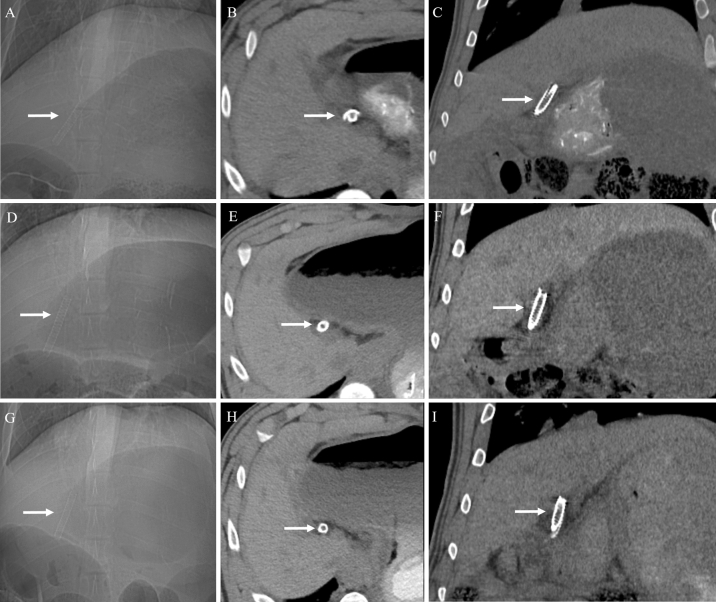

On follow-up non-contrast CT examination, there was no radiologic evidence of bile duct obstruction or leakage in any pig (n = 14). Furthermore, the stents were clearly visualized as radiopaque material, which made it easy to confirm the position and condition of the stents (Fig. 5). Among the six pigs in the stent group with 3-month follow-up, in one pig, the stent disappeared on the 3-month follow-up CT. Of the five pigs in the stent group with 1-month follow-up, two pigs showed disappearance of stents on the 1-month follow-up CT. This might be due to distal migration of the stents following bile duct peristalsis. In addition, among the 11 pigs in the stent group, three pigs in the stent group with 3-month follow-up had a stent fracture on the 2-month follow-up CT (Fig. 6).